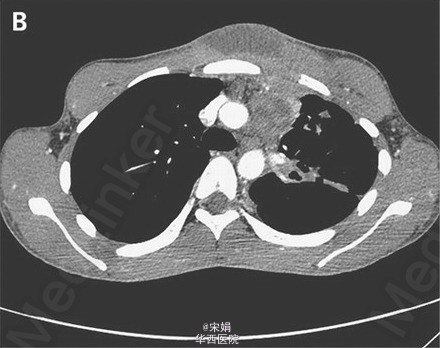

18岁男性,咳嗽3+月,伴淡红色痰、体重下降、发热。一周内前胸壁出现一局限性红肿。胸部CT示哑铃型脓肿(皮下脓肿通过窦道与深部脓肿相通:前胸壁皮下脓肿→左侧纵膈淋巴结内脓肿)、左肺上叶广泛肺实质异常。痰涂片、痰培养提示为结核分枝杆菌,HIV(-)。接受标准抗结核治疗8周,感染情况进展,皮下脓肿增大、出现红斑、有波动性。立即给予脓肿切开引流术。术后未再出现恶化征象,但脓肿引流完全后仍需行整形手术达到美观效果。